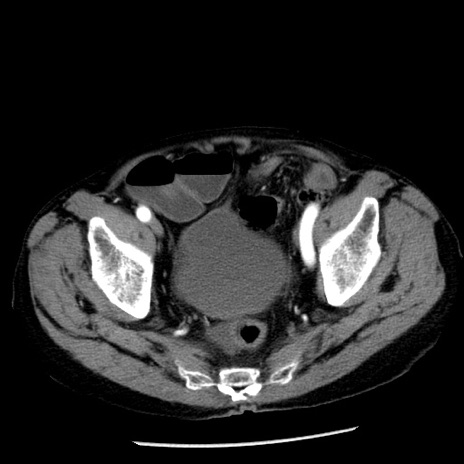

症例26(横断像)

【症例】80歳代男性

【主訴】嘔吐

【現病歴】昨晩2回嘔吐あり、今朝になっても嘔吐あり。来院。

【既往歴】胃潰瘍

【身体所見】意識清明、BT 37.6℃、BP 166/95mmHg、HR 100bpm、SpO2 97%、腹部:平坦・軟、腸蠕動音聴取良好、圧痛なし。

【データ】WBC 21900、CRP 1.46